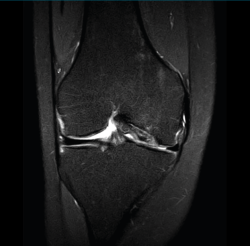

1.1. Meniscos

Figura 30. Corte de secuencia sagital T2 Fat-Sat de resonancia magnética de rodilla: menisco externo normal.

Se identifican como estructuras hipointensas en todas las secuencias, con asta anterior y posterior de morfología triangular.

Figura 31. Corte de secuencia sagital T2 Fat-Sat de resonancia magnética de rodilla: menisco interno normal.

La RM es la técnica de elección en el diagnóstico de la patología meniscal(17)(Figuras 30, 31, 32, 33, 34 y 35).

Figura 32. Corte de secuencia coronal T2 Fat-Sat de resonancia magnética de rodilla: rotura de menisco interno horizontal.

Figura 33. Corte de secuencia sagital T2 Fat-Sat de resonancia magnética de rodilla: menisco interno con cambios mucoides.

Figura 34. Corte de secuencia sagital T2 Fat-Sat de resonancia magnética de rodilla: rotura en asa de cubo desplazada al asta anterior del menisco externo.

Figura 35. Corte de secuencia coronal y sagital de resonancia magnética de rodilla: rotura en asa de cubo del menisco interno con fragmento desplazado al intercóndilo.